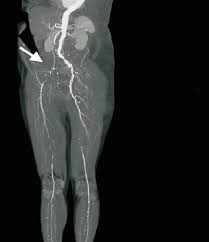

BT anjiyografi / MR anjiyo: infrarenal aorta + iliak darlık/oklüzyon

Radyografik özellikler

BT anjiyografi genellikle değerlendirme için en iyi yöntemdir. BT’nin mümkün olmadığı hastalarda, kontrastlı MR anjiyografi iyi bir seçenek olabilir

BT anjiyografi

Bu yöntem, stenoz ve tıkanıklığın yerinin doğrudan anatomik olarak görüntülenmesine olanak tanır. Ayrıca, iç organ arterlerini etkileyen eşlik eden tıkayıcı bir hastalığın varlığını, kollateralizasyonun tipini ve kapsamını ve stent greft yerleştirilmesine uygun en proksimal ve distal arter segmentlerinin seviyesini değerlendirmeye izin verir.